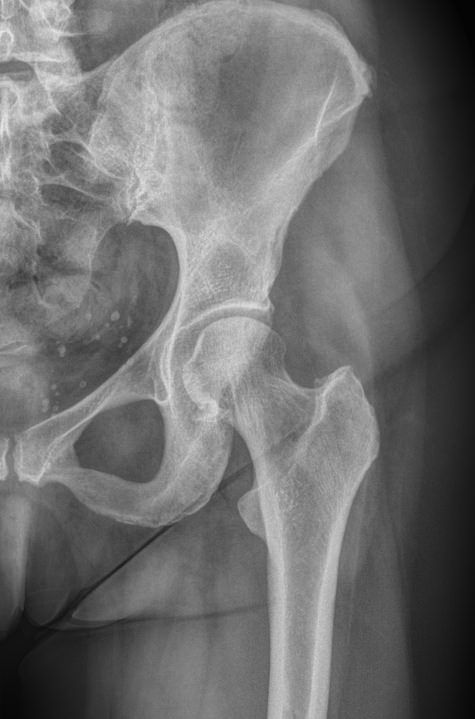

Рентгенография ― один из наиболее информативных методов диагностики патологий тазобедренных суставов. Это доступная, распространенная и неинвазивная диагностика, несущая минимальное количество ионизирующего излучения. В результате исследования можно обнаружить изменения, как травматические, так и воспалительного характера, происходящие с самыми крупными сочленениями костей в организме человека.

Снимок обоих суставов нужен при неспецифическом  воспалении, туберкулезе, дистрофических и дегенеративных процессах, а также для исключения травматических повреждений ― вывихов. При подозрении на врожденную аномалию рентгенограмма также необходима.

• Состояние суставных щелей, их симметричность и особенности;

• Соответствие вертлужных впадин головкам бедренных костей;

• Структуру костной ткани и патологические изменения в ней в области суставов;

• Ядра окостенения у детей;

• Врожденные аномалии, например, дисплазию;

• Переломы и вывихи;

• Новообразования.